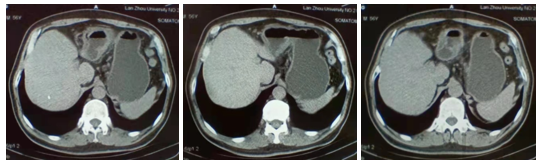

影像学检查:2021.02.20腹部CT:胃窦癌(T3/4期)幽门上下多发小淋巴结。

图1 腹部CT

增强CT检查(2021.4.14):胃角、胃窦小弯侧局部胃壁增厚,考虑胃癌(T3N0M0)。

增强CT检查(2021.6.9):胃腔充盈良好,胃壁未见局限性增厚,胃窦部胃壁未见异常强化(见图5)。

图5 增强CT